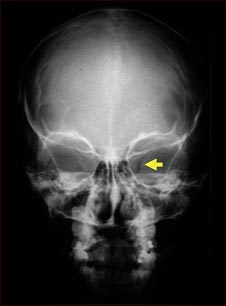

Neurofibromatosis I, agrandamiento de la abertura óptica

Esta radiografía muestra el cráneo de un niño con neurofibromatosis (NF-1). Este niño desarrolló trastornos visuales y se le diagnosticó un glioma (tumor en un nervio) en el nervio óptico. El tumor ha ensanchado el orificio óseo (foramen óptico), a través del cual pasa el nervio óptico, tal como se puede observar en la parte derecha de la imagen.